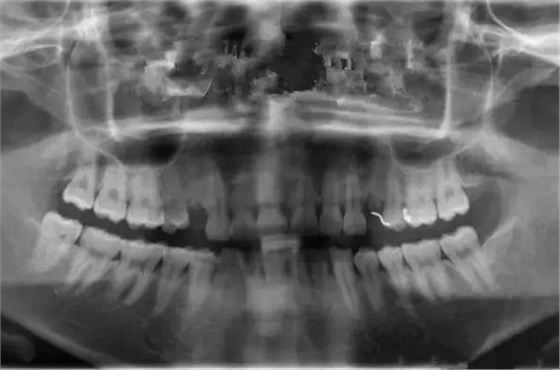

治療之前,先做口腔全景CT片:

從CT片中可明顯看到右側(cè)上頜一雙尖牙缺失,但是牙槽骨條件良好、無炎癥,做種植比較簡單、也符合該客戶不傷鄰牙、方便的需求。